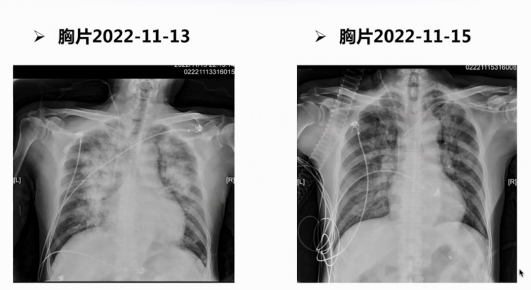

入院第六天,患者突发呼吸困难,心率105次/分,呼吸频率22次/分,血压降至89/48 mmHg,脉搏氧饱和度在鼻导管吸氧5 L/min下仅90%,双肺满布干湿啰音,血气分析提示pH 7.33、二氧化碳分压38 mmHg、氧分压62 mmHg。胸片显示双肺呈明显肺水肿表现,心电图可见V4-V6导联T波高尖,心肌损伤标志物未提示CK-MB进一步升高,白细胞、血红蛋白、血钾及肝肾功能无明显异常,仅低密度脂蛋白胆固醇轻度升高。床旁超声心动图因声窗不清,仅见后侧壁室壁节段性运动异常、心脏射血分数45%-50%、二尖瓣反流,但未明确病因。

经分析排除再发心肌梗死、肺部感染等常见诱发心衰原因,考虑心肌梗死后机械并发症。进一步观察超声心动图,发现二尖瓣后叶瓣尖位置团块状回声、二尖瓣后叶脱垂及偏心性血流,印证机械并发症可能。随后通过植入IABP、无创呼吸机辅助通气及床旁心衰超滤脱水治疗,患者呼吸困难缓解,超声心动图显示二尖瓣后叶重度偏心性反流、反流束偏向前叶,行经食道超声心动图确诊二尖瓣后叶乳头肌断裂、二尖瓣反流量达重度反流程度,三维超声重建显示二尖瓣脱垂范围及脱垂距离,最终明确诊断为急性心肌梗死后第6天并发二尖瓣乳头肌断裂。

因患者既往2次脑梗死史、合并严重脑血管狭窄,STS手术风险评分29.5%,属极高危组,围术期卒中风险高,经多学科讨论决定行经导管二尖瓣缘对缘修复术。术中经食道超声监测,单枚夹子成功植入,二尖瓣反流由重度转为轻度,且未出现二尖瓣严重狭窄。术后患者心脏射血分数一度下降至30%,经正性肌力药物、利尿及扩血管治疗,术后第二天恢复到45%,第四天患者出院。